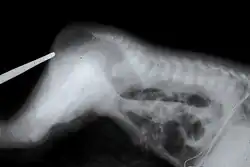

| An X-ray showing imperforate anus | |